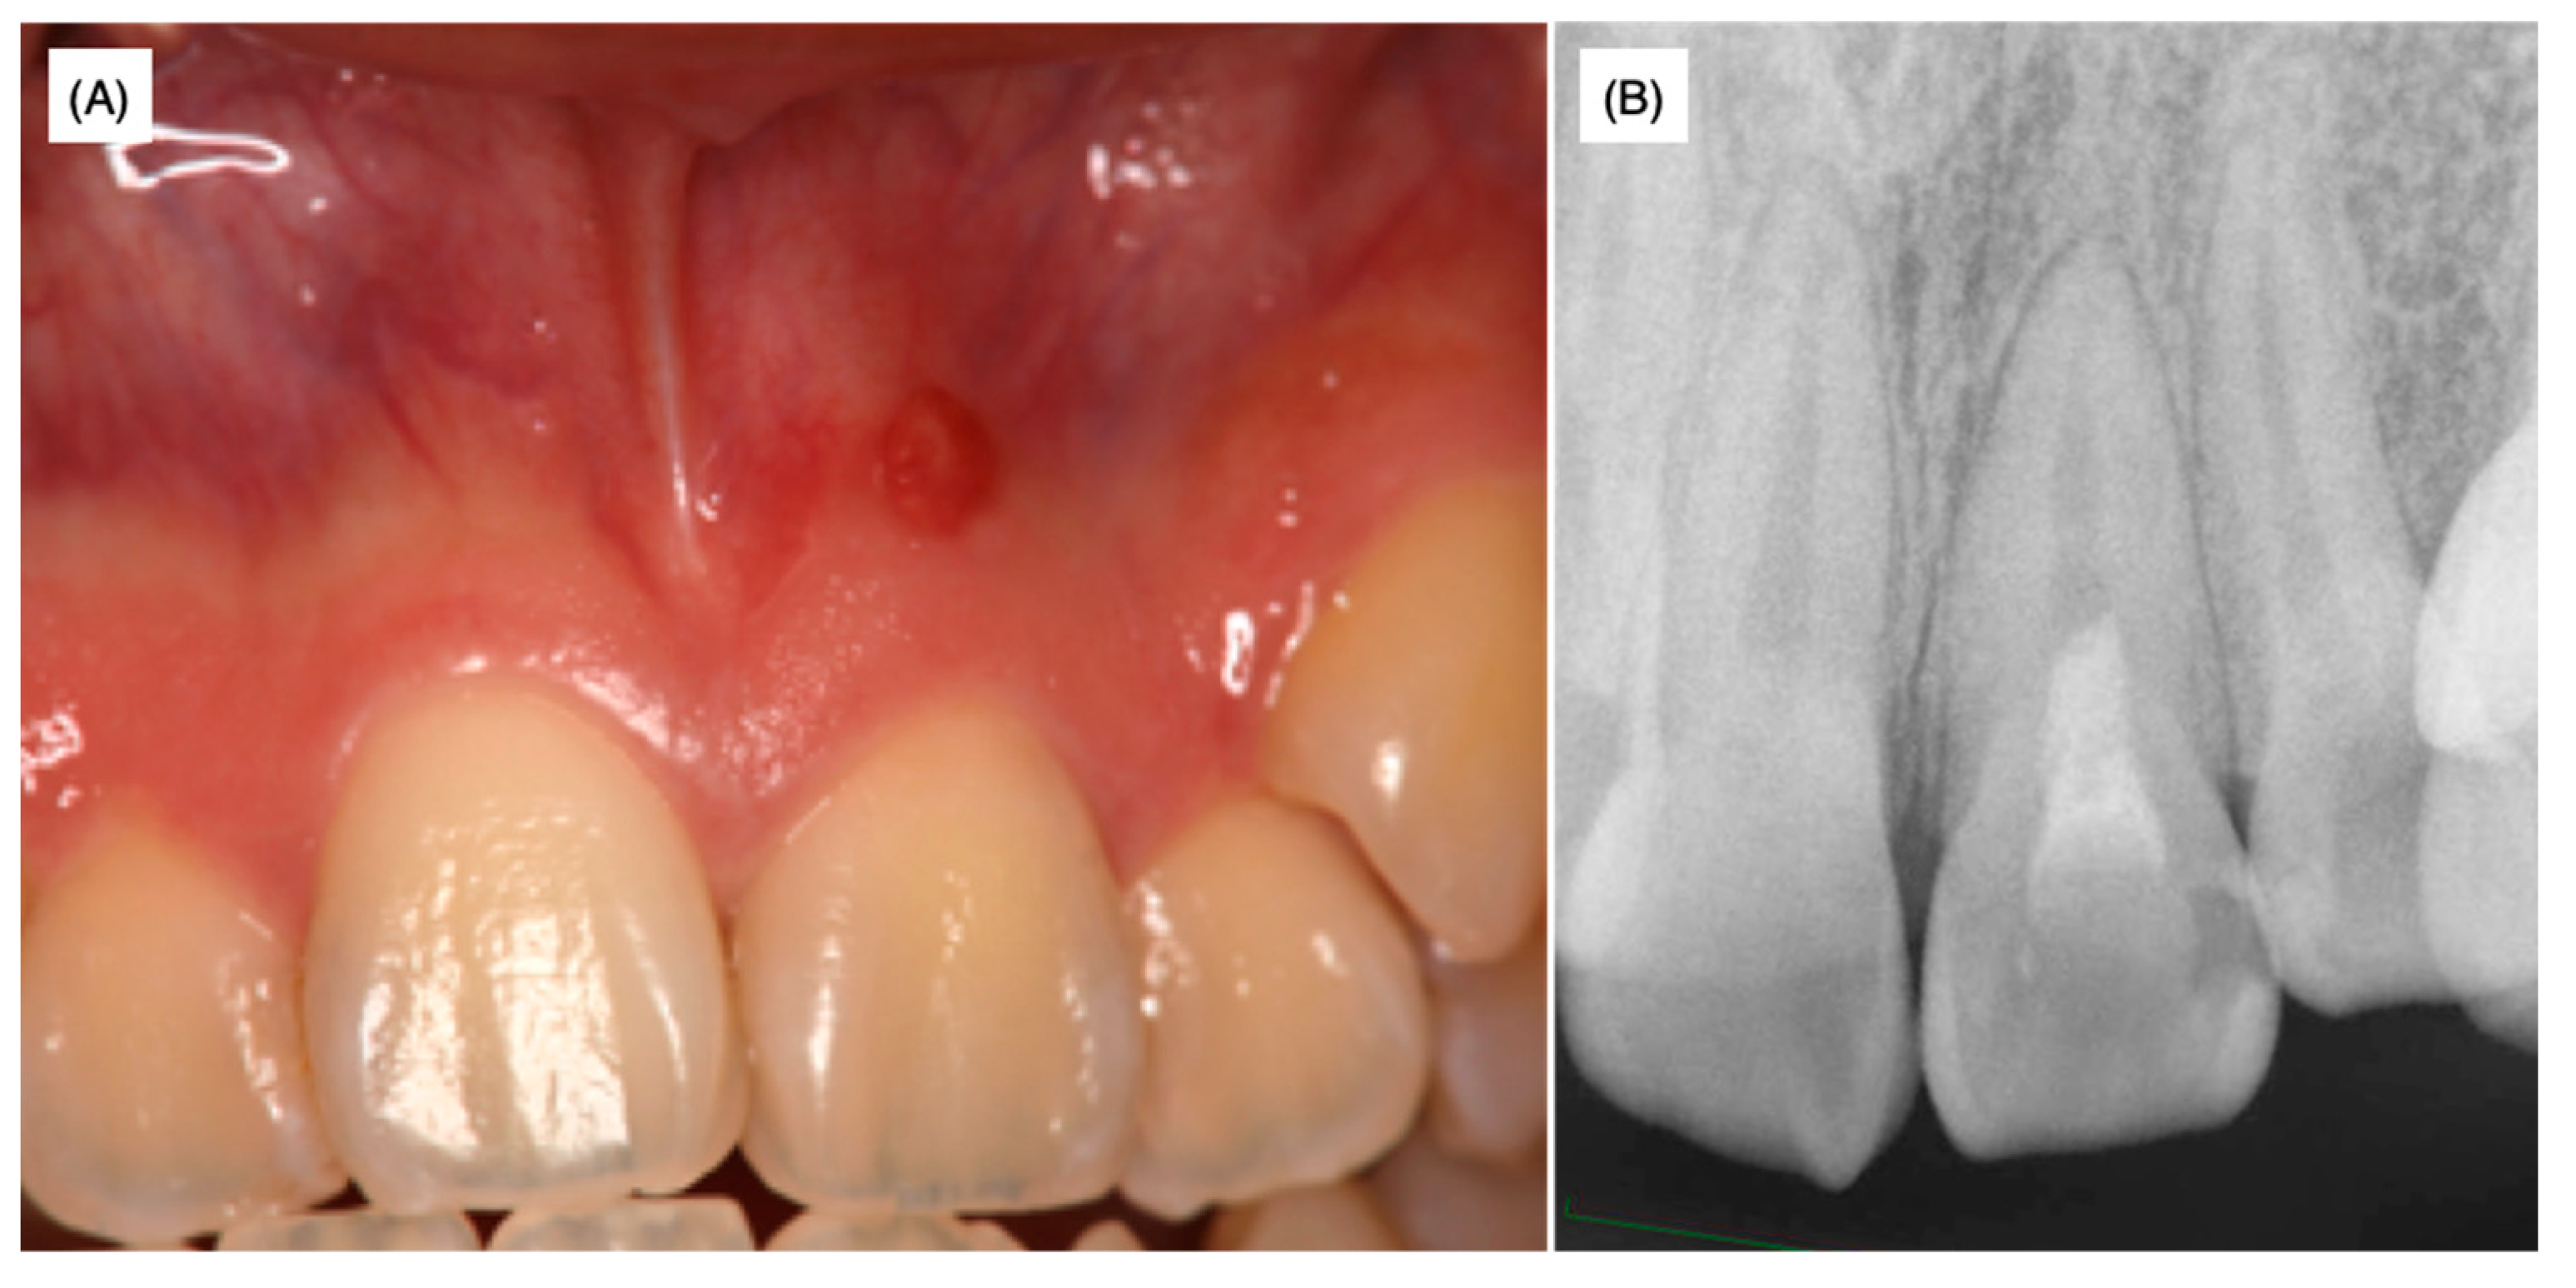

A female patient aged 18 years was referred to a private dental clinic for cosmetic problems caused by a black-colored left maxillary central incisor. As swelling in the attached gingiva surrounding the upper left maxillary incisor was observed, X-ray analysis was performed with and without the insertion of gutta-percha points (GC Dental Industrial Corp, Tokyo, Japan) in the sinus tract in order to identify the lesion area (Figure 1A,B).

Slight pressure pain and notable fistulization were identified in the swollen area. However, no spontaneous pain or significant perpendicular or horizontal percussion pain was identified. The probing depth of the left maxillary incisor was within 2 mm and tooth movement was within physiological limits; thus, root fracture was not assumed. The palatal side was sealed with hydraulic cement. Dental radiographs taken at the first visit to the university hospital as well as radiographs provided by the private dental clinic revealed that the width of the root canal adjacent to the apex of the left maxillary incisor was narrower than that of the maxillary right central incisor (Figure 1 and Figure 2B). The upper two-thirds of the crown side were filled with Calcipex II® from the previous treatment. Moreover, the width of the periodontal ligament space was slightly enlarged (Figure 1 and Figure 2B).

Figure 1. X-ray films without (A) and with (B) the insertion of gutta-percha points when the patient was 18 years and 8 months old. These X-rays were taken at a private dental clinic before the patient came to our university dental hospital.